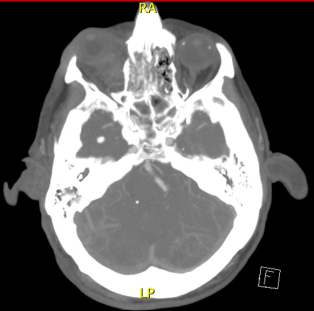

CT Head, CT Angiogram

When patient first presents to the emergency room, CT head without contrast and CT angiogram are helpful in identifying intracranial bleeding and vascular lesions. CTA of the head and the neck are also helpful in identifying vascular injuries.

Based on past literature and ED triaging experience, pseudoaneurysm may expand quickly in its early phase of development, which may mimic an expanding hematoma. [11] However, the precise timing of OAPA progression may not manifest until up to 24 hours after the initial injury. Follow-up imaging will be helpful in monitoring the size of progression and determining next step management. Unlike hematomas, pseudoaneurysms will stabilize in size without active contrast extravasation. [11]